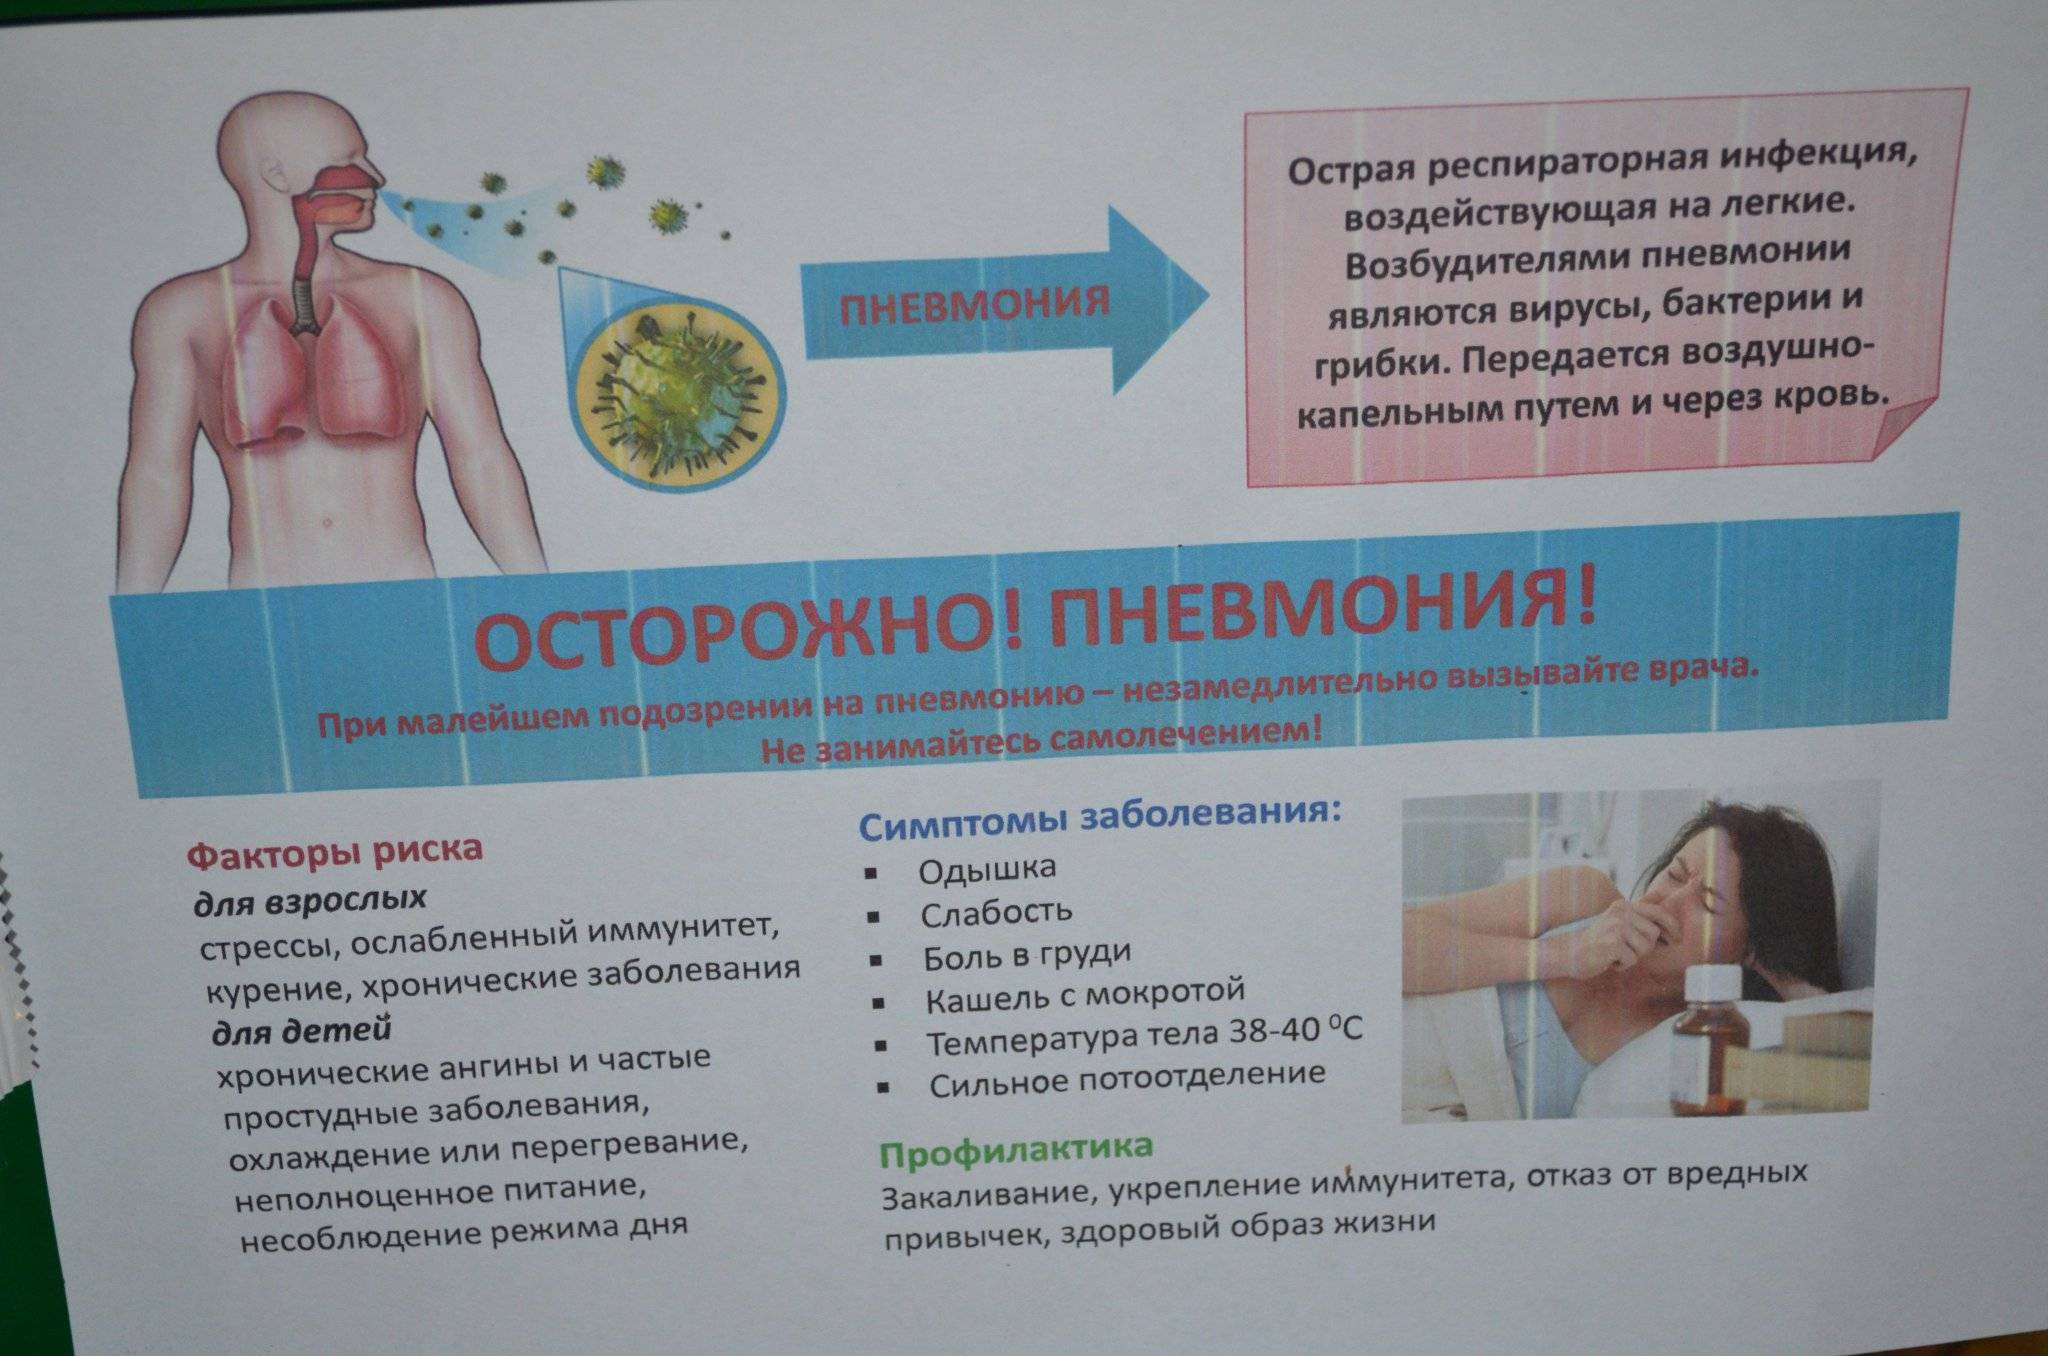

Острая внебольничная пневмония по МКБ-10: признаки и примеры